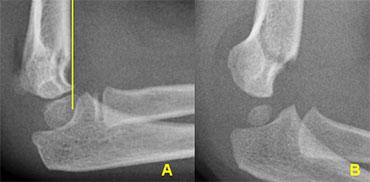

Normal medial epicondyle projecting posteriorly. Notice radial head dislocation and olecranon fracture

Medial Epicondyle avulsion

Mỏm trên lồi cầu trong là một mấu xương vì nó không đóng góp vào sự tăng trưởng theo chiều dọc của xương cánh tay.

Nó nằm ở phía sau của khuỷu tay.

Trên hình chiếu thẳng bên, đặc biệt nếu cánh tay ở tư thế xoay trong, nó có thể chiếu ra phía sau đến mức có thể gợi ý một tổn thương bong điểm bám (hình ảnh).

Tuy nhiên, các tổn thương bong điểm bám thường nằm ở vị trí xa hơn và phía trước hơn.

The radial epiphysis is slipped (arrows). The radiocapitellar line does not pass through the capitellum indicating dislocation and there is a fracture of the olecranon

Gãy cổ xương quay cũng như trật đầu xương quay trong 50% trường hợp có liên quan đến các tổn thương khuỷu tay khác.

Thường gặp nhất là gãy mỏm khuỷu.

Khi đầu xương quay còn rất nhỏ, trượt đầu xương quay có thể bị bỏ sót (hình).

LEFT: an obvious radial dislocation. No fracture of the ulna (Monteggia) was foundRIGHT: a subtle radial head dislocation. Associated olecranonfracture is seen on carefull inspection

Dislocations of the Radial head

Trật khớp đầu xương quay có thể rất rõ ràng.

Tuy nhiên, không hiếm trường hợp những trật khớp này khó nhận thấy và dễ bị bỏ sót.

Trong mọi trường hợp, cần tìm kiếm các tổn thương kèm theo.

Trong mô tả ban đầu của Monteggia, có sự trật khớp đầu xương quay kết hợp với gãy thân xương trụ đoạn gần.

Tuy nhiên, gãy xương ở bất kỳ vị trí nào dọc theo xương trụ cũng đã được ghi nhận.

Đặc biệt, gãy xương mỏm khuỷu kèm theo rất phổ biến (hình).